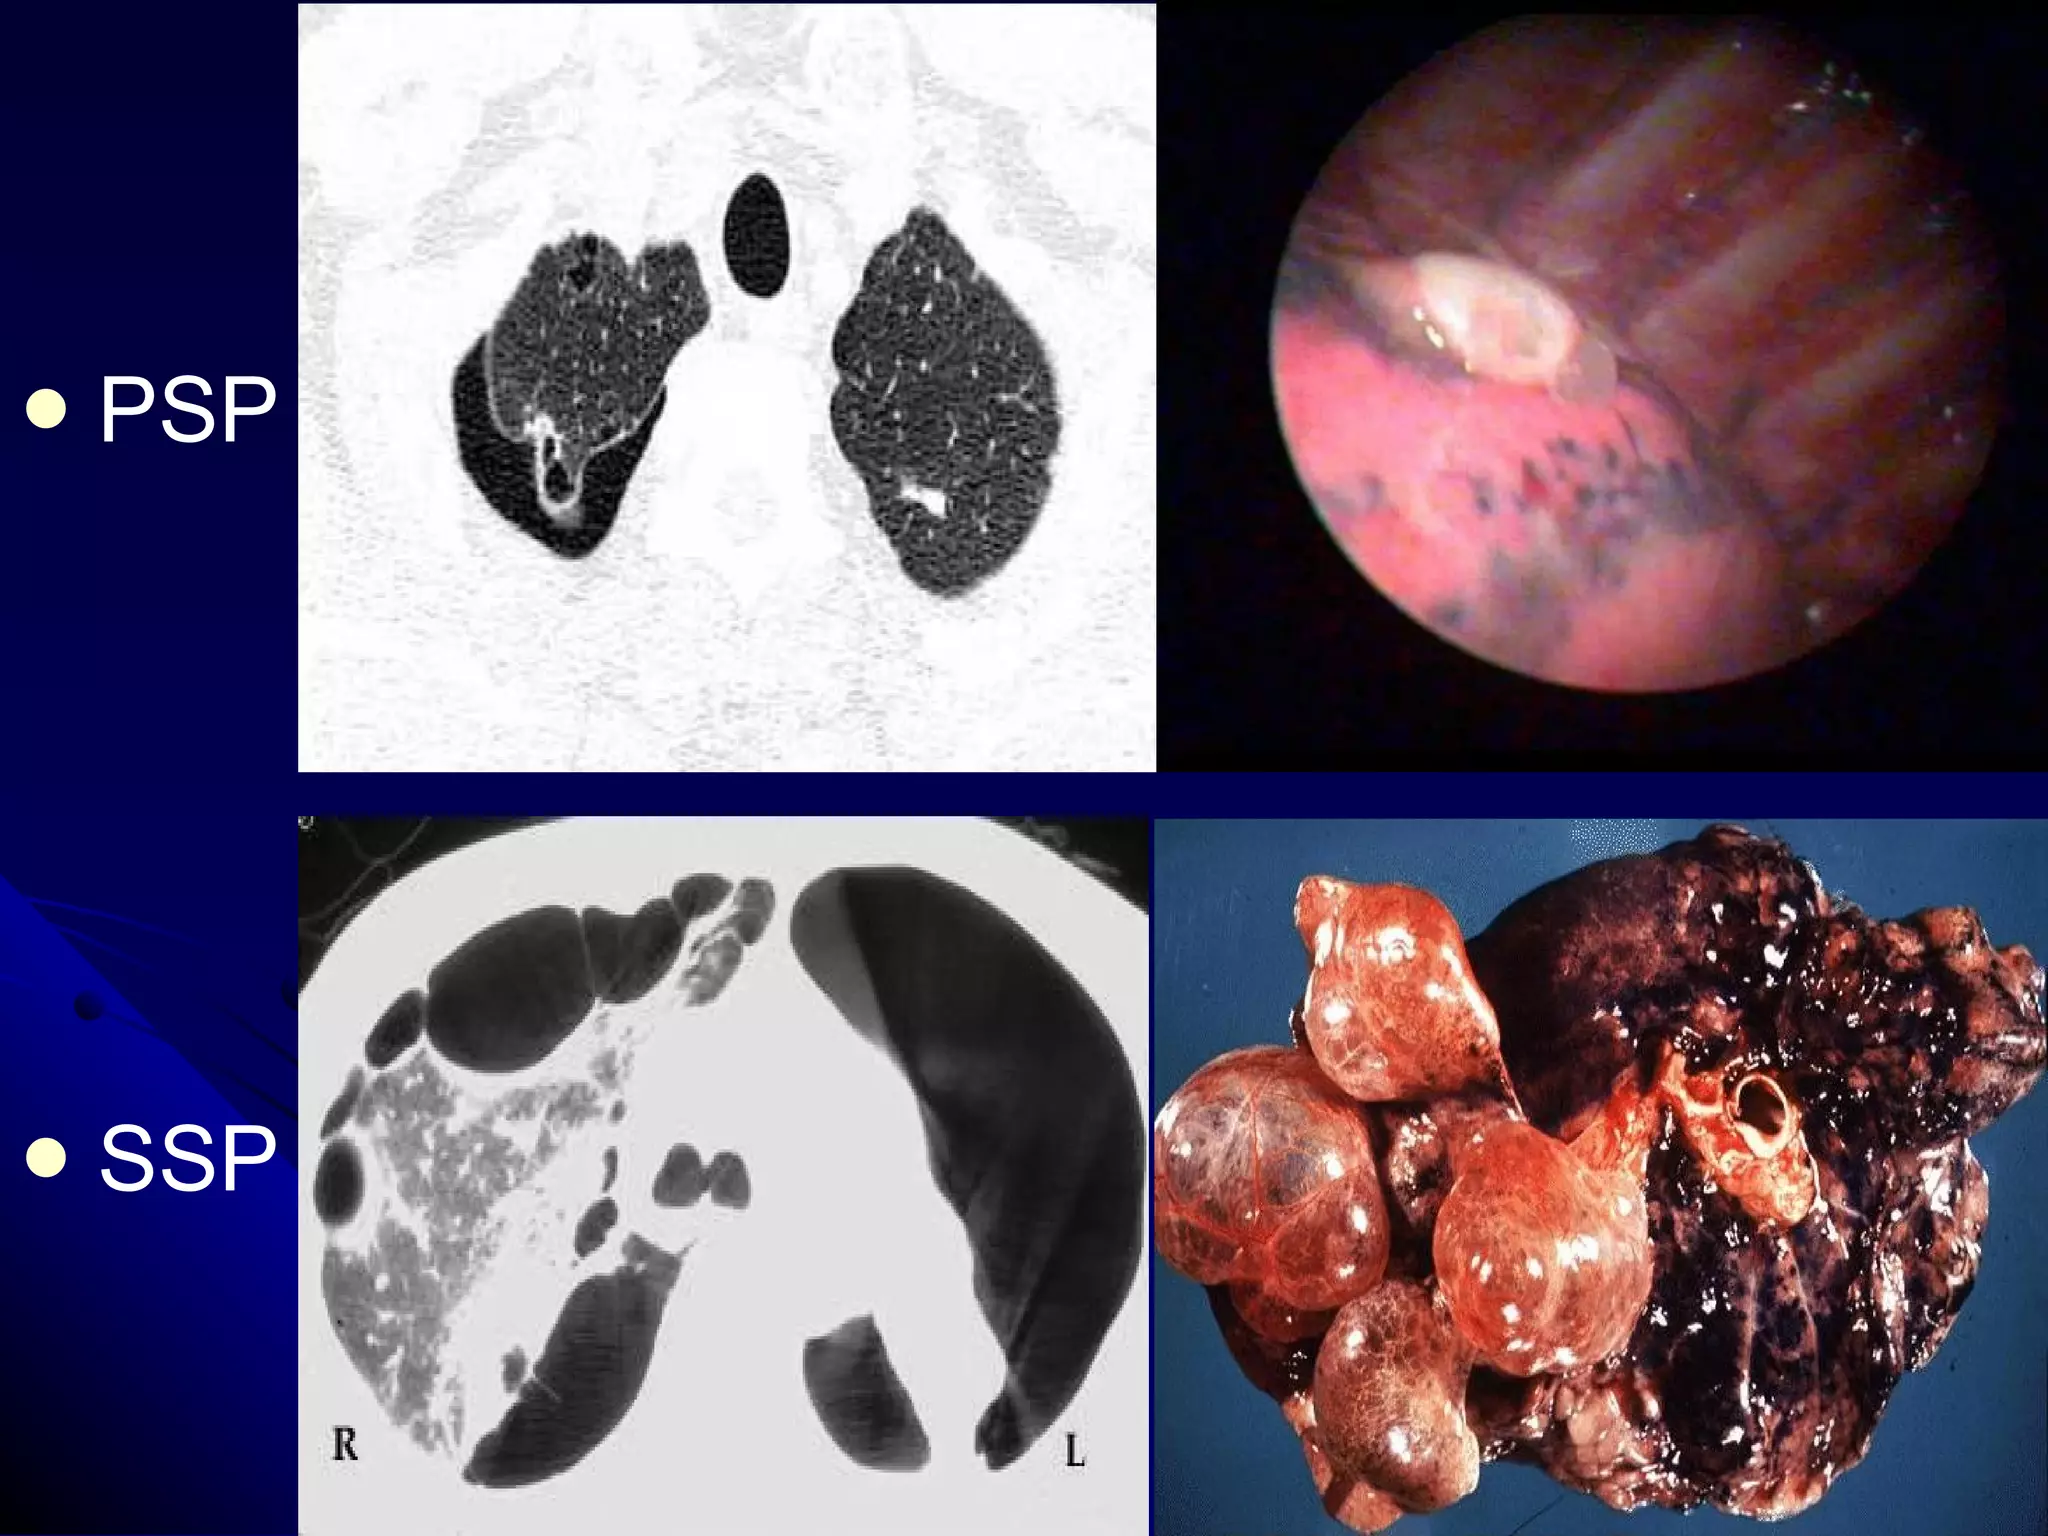

Spontaneous pneumothoraces are subclassified as: Primary spontaneous pneumothorax (PSP) Healthy people, most young people Secondary spontaneous pneumothorax (SSP) Underlying diseases Chronic obstructive pulmonary disease (COPD), pulmonary tuberculosis Clinical typing of pneumothorax

PSP SSP

Spontaneous pneumothoraces aresubclassified as: Primary spontaneous pneumothorax (PSP) Healthy people, most young people Secondary spontaneous pneumothorax (SSP) Underlying diseases Chronic obstructive pulmonary disease (COPD), pulmonary tuberculosis Clinical typing of pneumothorax